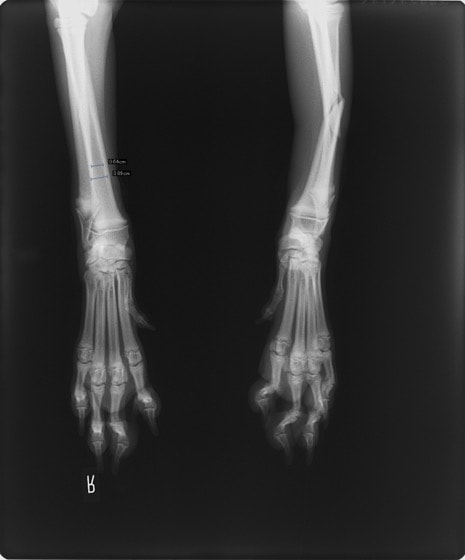

トイプードル 右遠位橈尺骨短斜骨折のALPSによる内固定

橈尺骨骨折 : 症例1 | 症例2 | 症例3 | 症例4 | 症例5 | 症例6 | 症例7

: 症例8 | 症例9 | 症例10 | 症例11 | 症例12 | 症例13 | 症例14

: 症例15 | 症例16 | 症例17 | 症例18 | 症例19 | 症例20 | 症例21